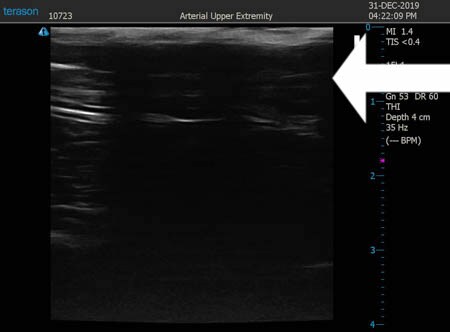

いつものように3Dタッチビュー(超音波)で

皮下脂肪層を評価してみましょう。

同様に右太もも前面。 ↓ ↓ ↓